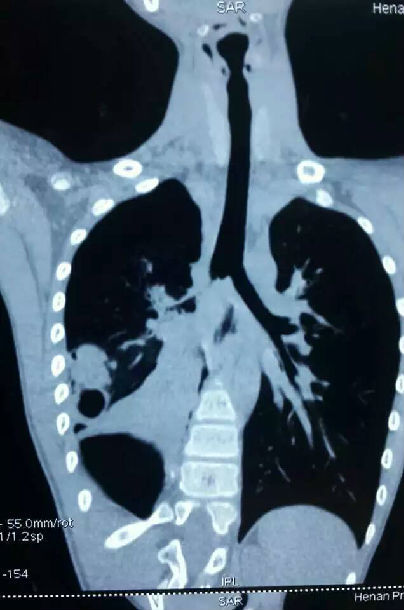

又是气管隆突下成形术。13岁男孩10月11日骑摩托车外伤,当时某大医院支气管镜发现右主支气管断裂,呼吸尚可,一直观察处理。待呼吸困难出现,又是医生介绍来求治,失去最佳治疗时机,炎症增生粘连,像钢板一样,仔细解剖5小时,手术顺利完成。

从10月1日起,为4例外伤性气管或主支气管损伤病人手术,1例伤后立即手术,虽损伤严重,但损伤新鲜,故处理较容易;另外3例都是损伤部肉芽增生,炎症粘连严重,解剖困难,易损伤周围脏器,如今日手术,伤后立即手术,右主支气管成形即可,今花5小时解剖,惊险连连,还要做隆突切除成形,术后也容易出现严重并发症。